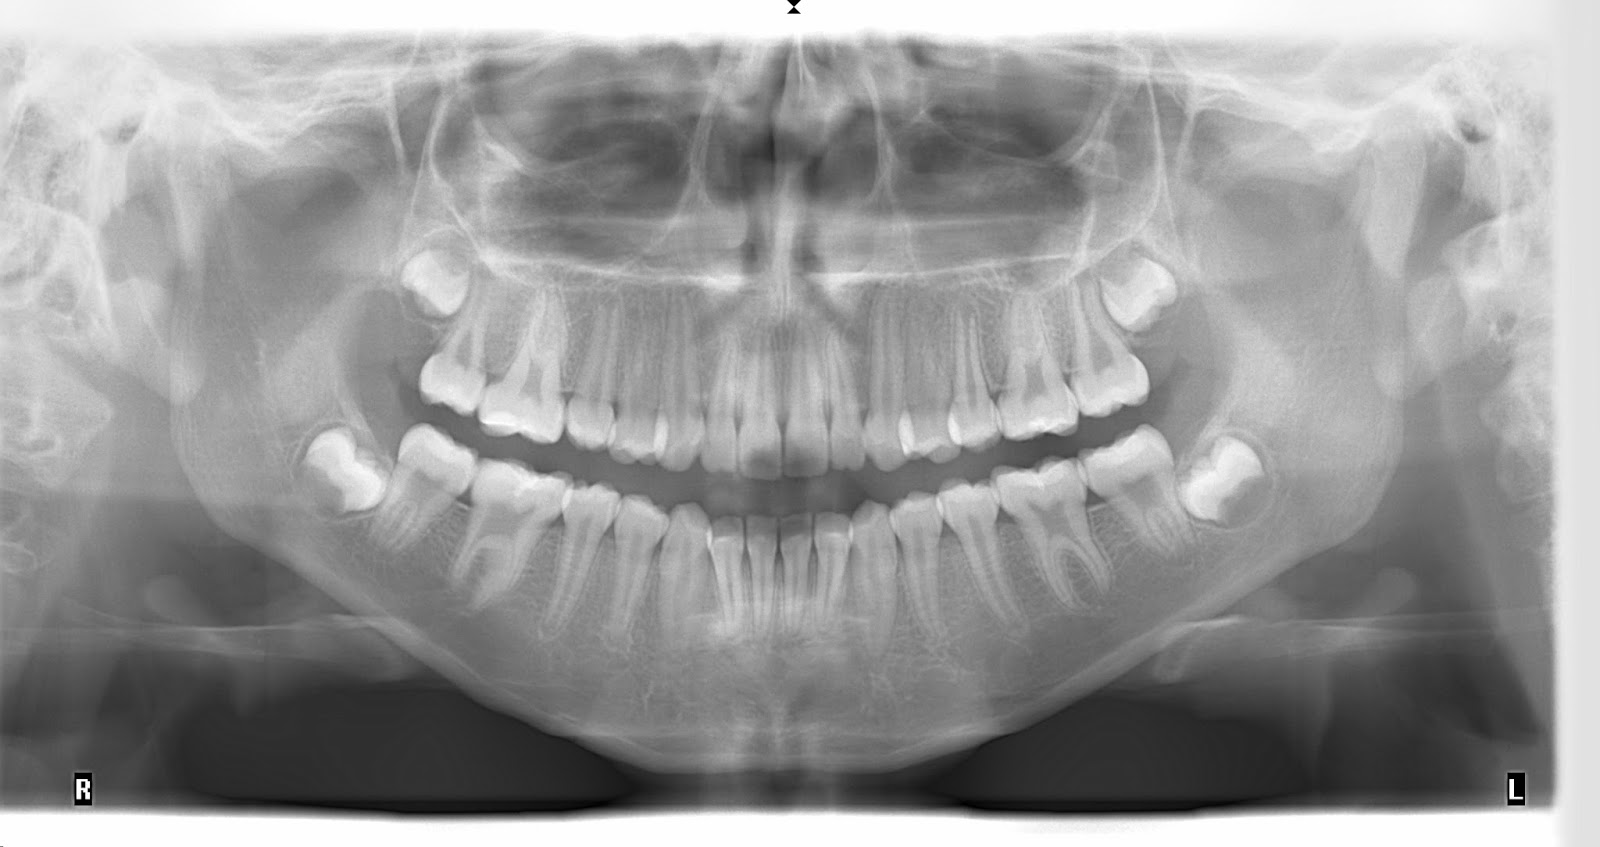

A radiografia panorâmica é muito indicada para quem tem problemas ortodônticos, isto é, disfunções no crescimento e no desenvolvimento dos dentes. O exame compõe a documentação usada pelo dentista para avaliar o caso — a partir de uma imagem dos elementos dentários e da parte óssea da boca — e, claro, indicar o melhor tratamento.. O modelo básico de um aparelho de radiografia panorâmica consiste em um tubo de imagem acoplado a um braço horizontal que pode ser direcionado para um dos lados do rosto do paciente, enquanto o braço horizontal oposto, que aponta para o outro lado, contém o filme ou detector de raios X. Normalmente, a cabeça do paciente é posicionada.